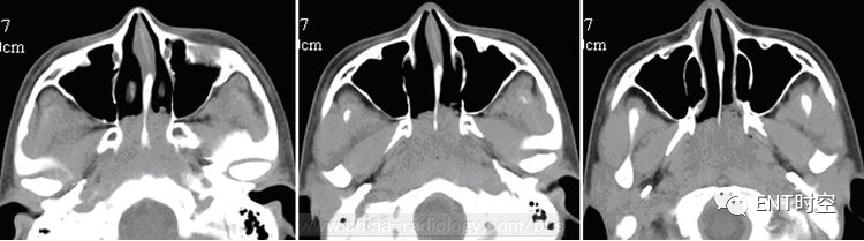

男,14岁,鼻塞,夜间打鼾、张口呼吸10年。

(一)影像所见:CT平扫鼻咽顶后壁可见软组织密度影,肿块几乎占满整个咽腔、并部分向双侧鼻腔蔓延,平扫呈等密度,增强扫描病变呈轻度强化。骨质未见明显破坏(二)病理诊断:(鼻咽部)腺样体淋巴组织增生伴粘膜慢性炎(三)鉴别诊断: 1.鼻咽癌; 2.淋巴瘤